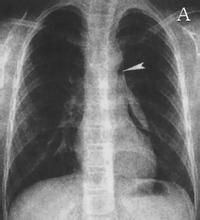

胸部X線檢查對明確縱隔氣腫的診斷具有決定性的意義。於後前位胸片上可見縱隔胸膜向兩側移位,形成與縱隔輪廓平行的高密度線狀陰影,其內側與縱隔輪廓間為含氣體的透亮影,通常在上縱隔和縱隔左緣較明顯上述徵象應與正常存在的縱隔旁狹窄的透亮帶(Mach帶)相區別,其鑑別要點在於Mach帶的外側並無高密度的縱隔胸膜影。此外,部分患者尚可在胸主動脈旁或肺動脈旁發現含氣透亮帶嬰兒當縱隔內氣體量較多時可顯示胸腺輪廓。縱隔氣腫在側位胸片上表現為胸骨後有一增寬的透亮度增高區域,將縱隔胸膜推移向後呈線條狀陰影,心臟及升主動脈前緣與胸骨間距離增大。X線檢查尚可清晰地顯示同時存在的氣胸以及下頸部和胸部皮下氣腫胸部CT檢查:胸部CT因不受器官重疊的影響,對縱隔氣腫顯示較清楚,尤其是當縱隔內積氣量較少,後前位胸片易於識別。治療